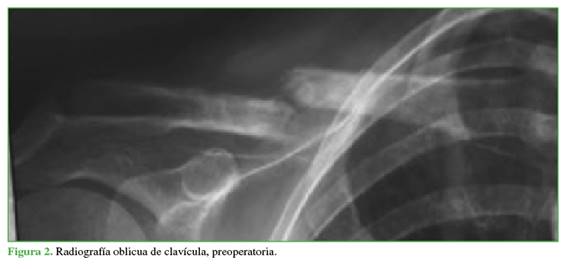

Se ubica al paciente en posición de silla de playa sobre una mesa radiolúcida. Se coloca un realce interescapular para simplificar la reducción del trazo de fractura (Figuras 1 y 2), el miembro superior afectado se deja libre para poder manipular durante la intervención. El arco en C se coloca en la cabecera para permitir la libre movilidad al cirujano. Antes de la cirugía, se dibujan, con guía radiológica, el trazo de fractura, los límites de la clavícula, se marca la incisión utilizando un implante de guía igual al que se colocará.